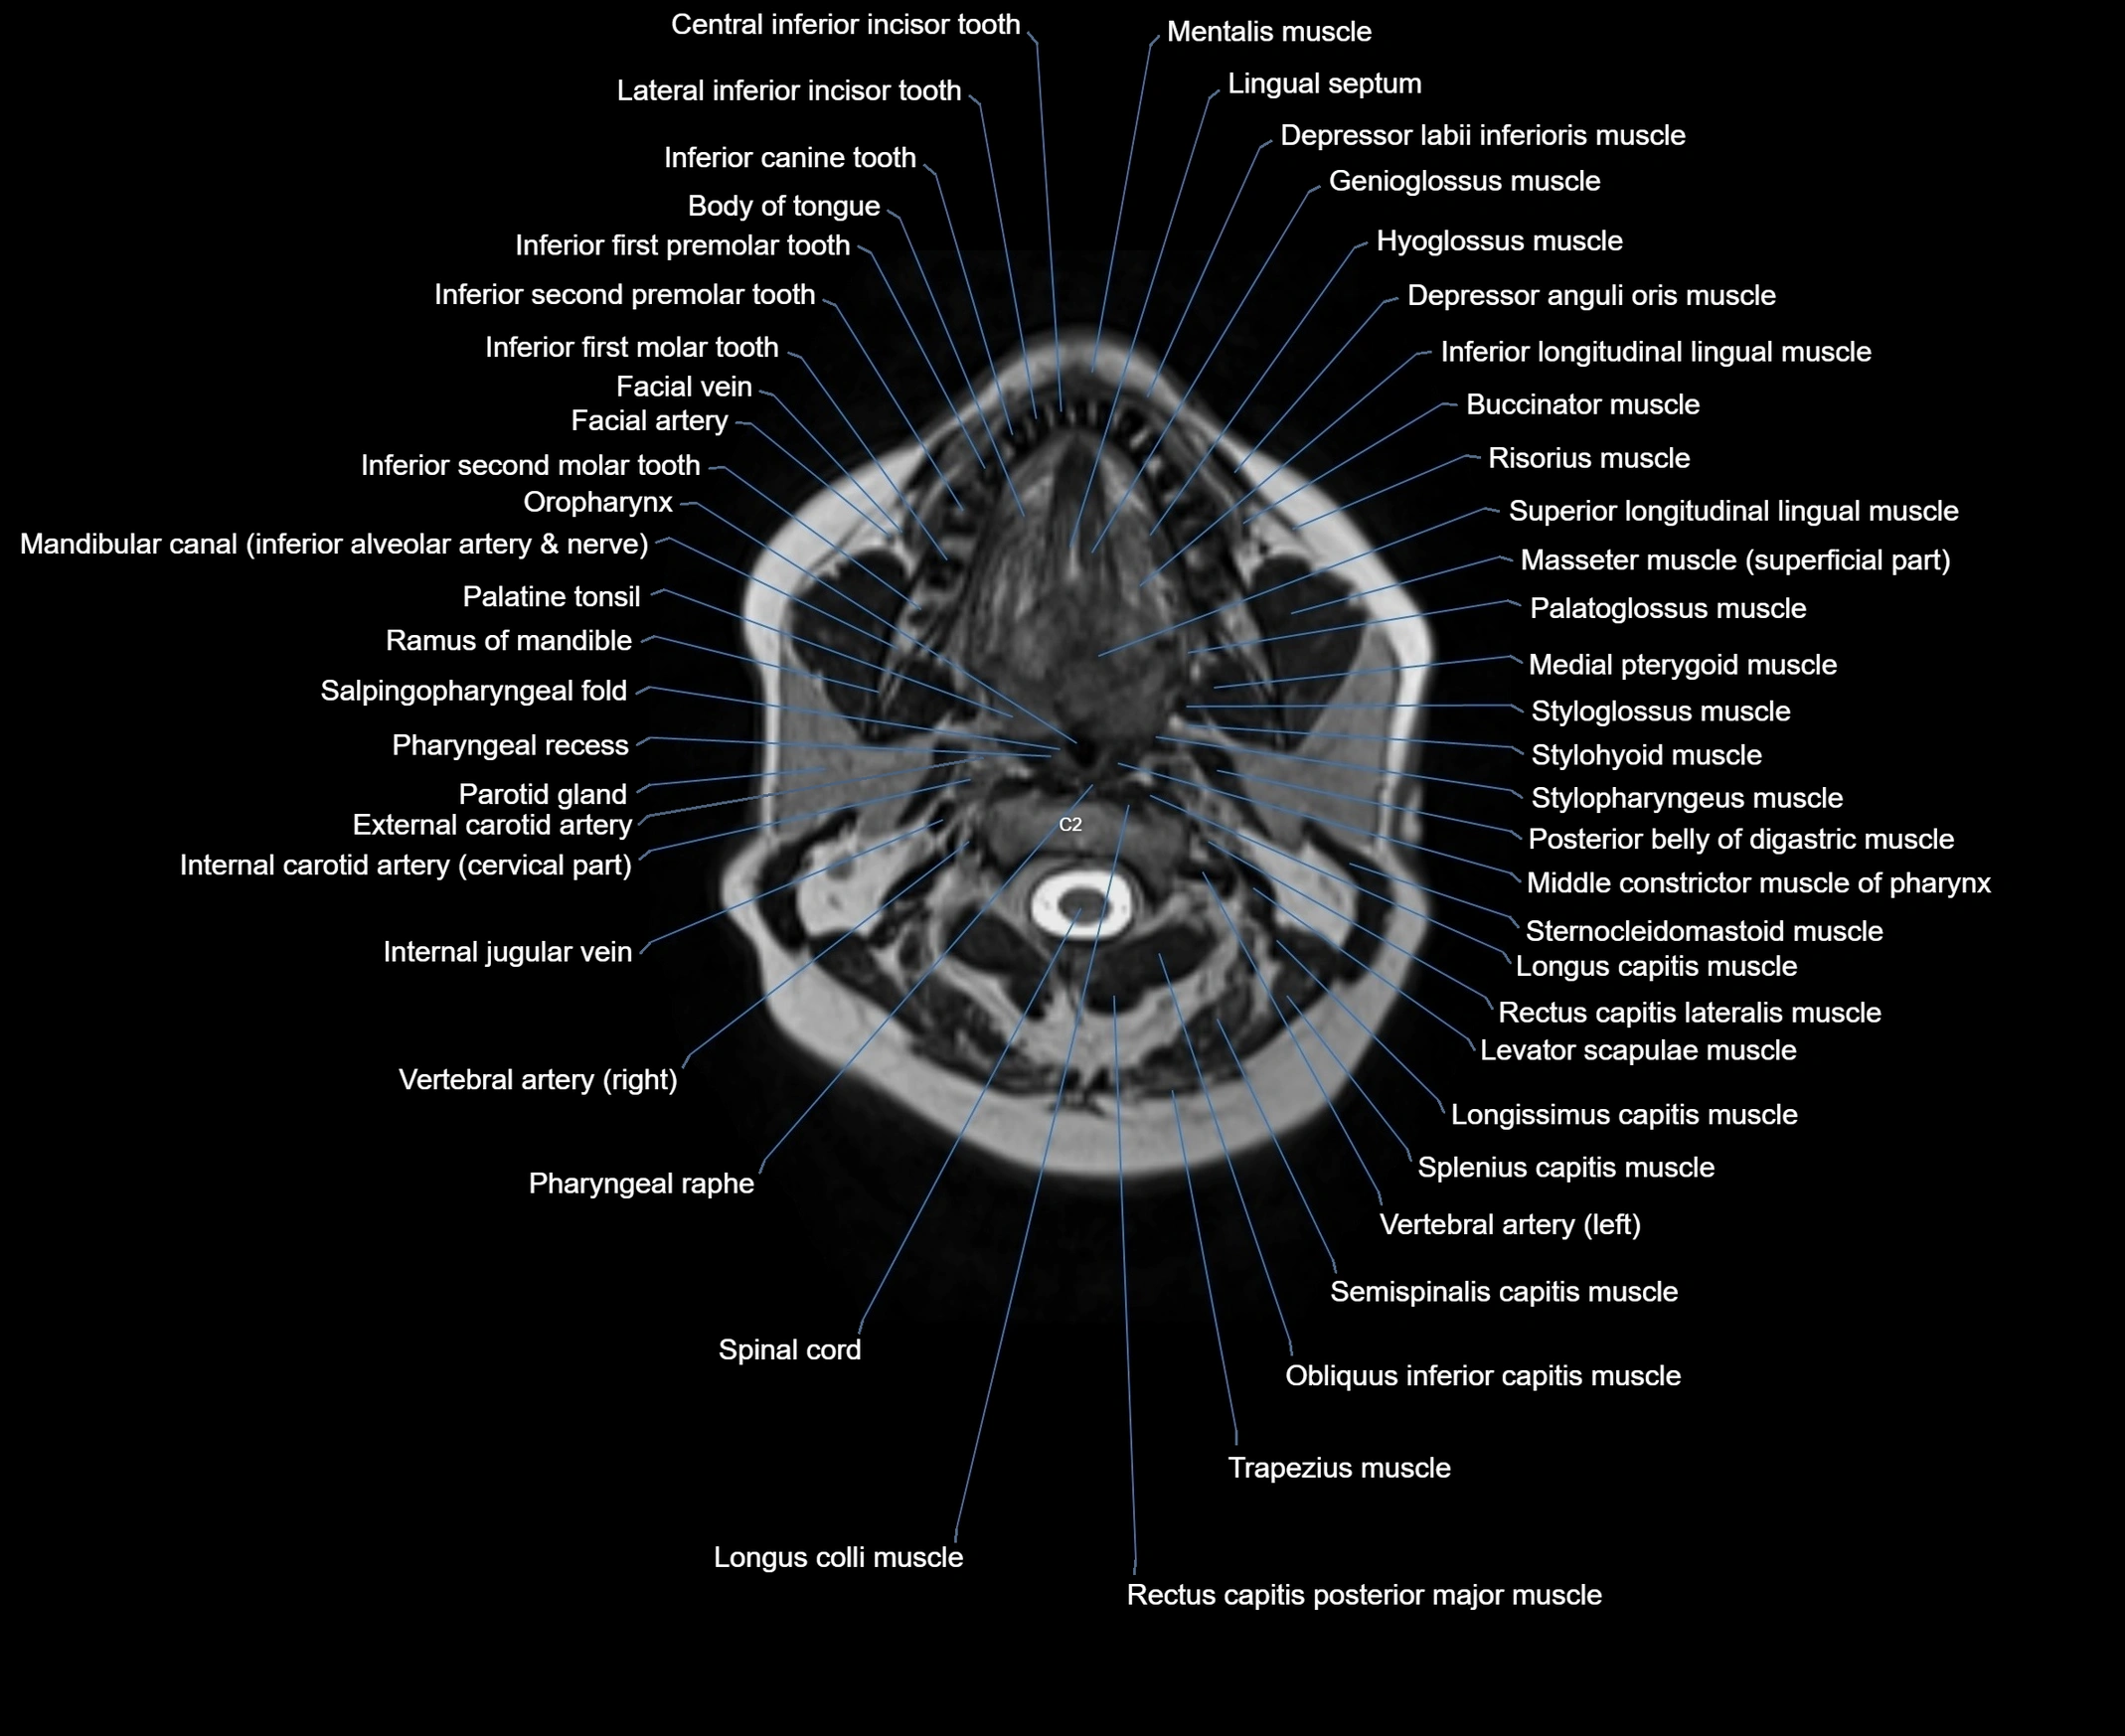

- Body of tongue

- Buccinator muscle

- Depressor labii inferioris muscle

- External carotid artery

- Genioglossus muscle

- Hyoglossus muscle

- Inferior longitudinal lingual muscle

- Inferior second molar tooth

- Inferior second premolar tooth

- Internal carotid artery

- Internal carotid artery (cervical part)

- Lateral inferior incisor tooth

- Mandibular canal

- Medial pterygoid muscle

- Middle constrictor muscle of pharynx

- Obliquus inferior capitis muscle

- Oropharynx

- Palatine tonsil

- Palatoglossus muscle

- Parotid gland

- Pharyngeal raphe

- Pharyngeal recess

- Posterior belly of digastric muscle

- Rectus capitis lateralis muscle

- Rectus capitis posterior major muscle

- Risorius muscle

- Salpingopharyngeal fold

- Spinal cord

- Sternocleidomastoid muscle

- Styloglossus muscle

- Stylopharyngeus muscle

- Superior longitudinal lingual muscle